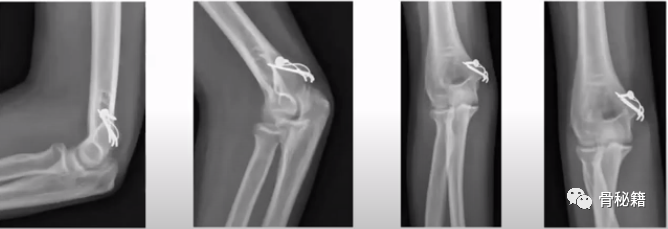

2、鹰嘴骨折

6、肱骨髁骨折